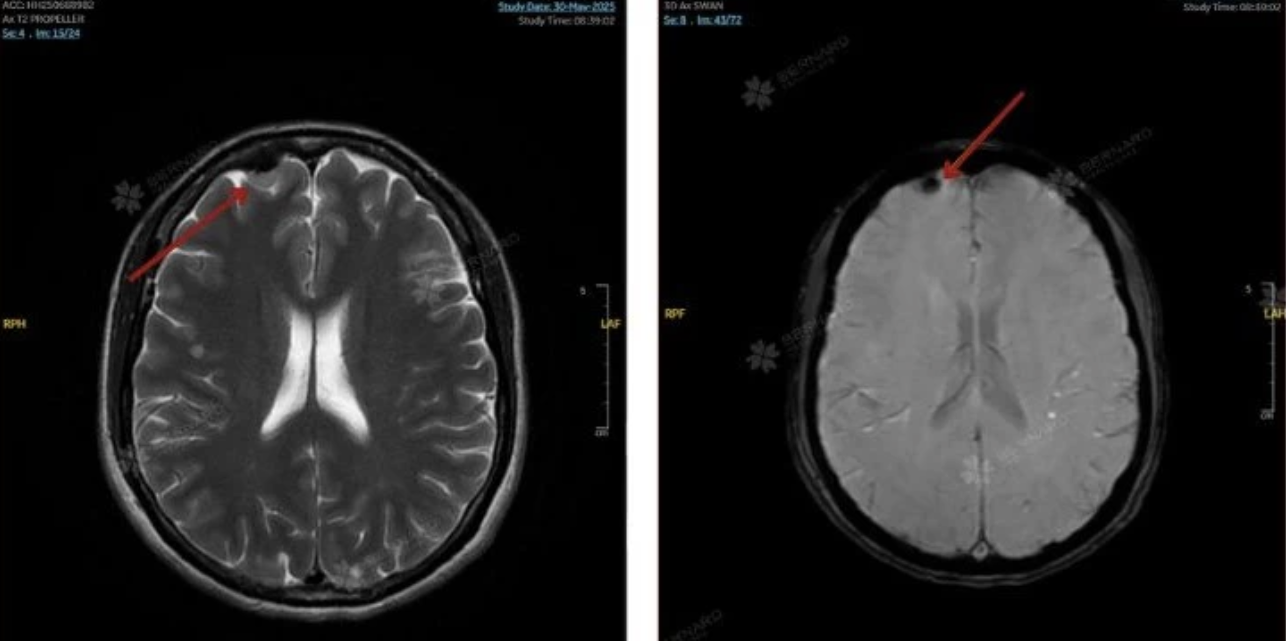

Kết quả MRI ghi nhận cùng lúc hai bất thường có ý nghĩa: túi phình động mạch cảnh trong phải kích thước khoảng 3 x 4 mm và u màng não có vôi hóa vùng trán phải, sát bản sọ. Cả hai tổn thương đều chưa gây triệu chứng nhưng tiềm ẩn rủi ro lớn nếu không theo dõi hoặc xử trí đúng thời điểm.

U màng não là khối u phát triển từ màng bao quanh não và tủy sống. Dù phần lớn lành tính, u vẫn có thể gây đau đầu kéo dài, giảm thị lực, nhìn đôi, động kinh mới khởi phát, yếu liệt tay chân, thay đổi hành vi, rối loạn trí nhớ, tăng áp lực nội sọ hoặc xuất huyết trong u. Nếu không được chẩn đoán và theo dõi sớm, u có thể gây tổn thương thần kinh vĩnh viễn hoặc đe dọa tính mạng.